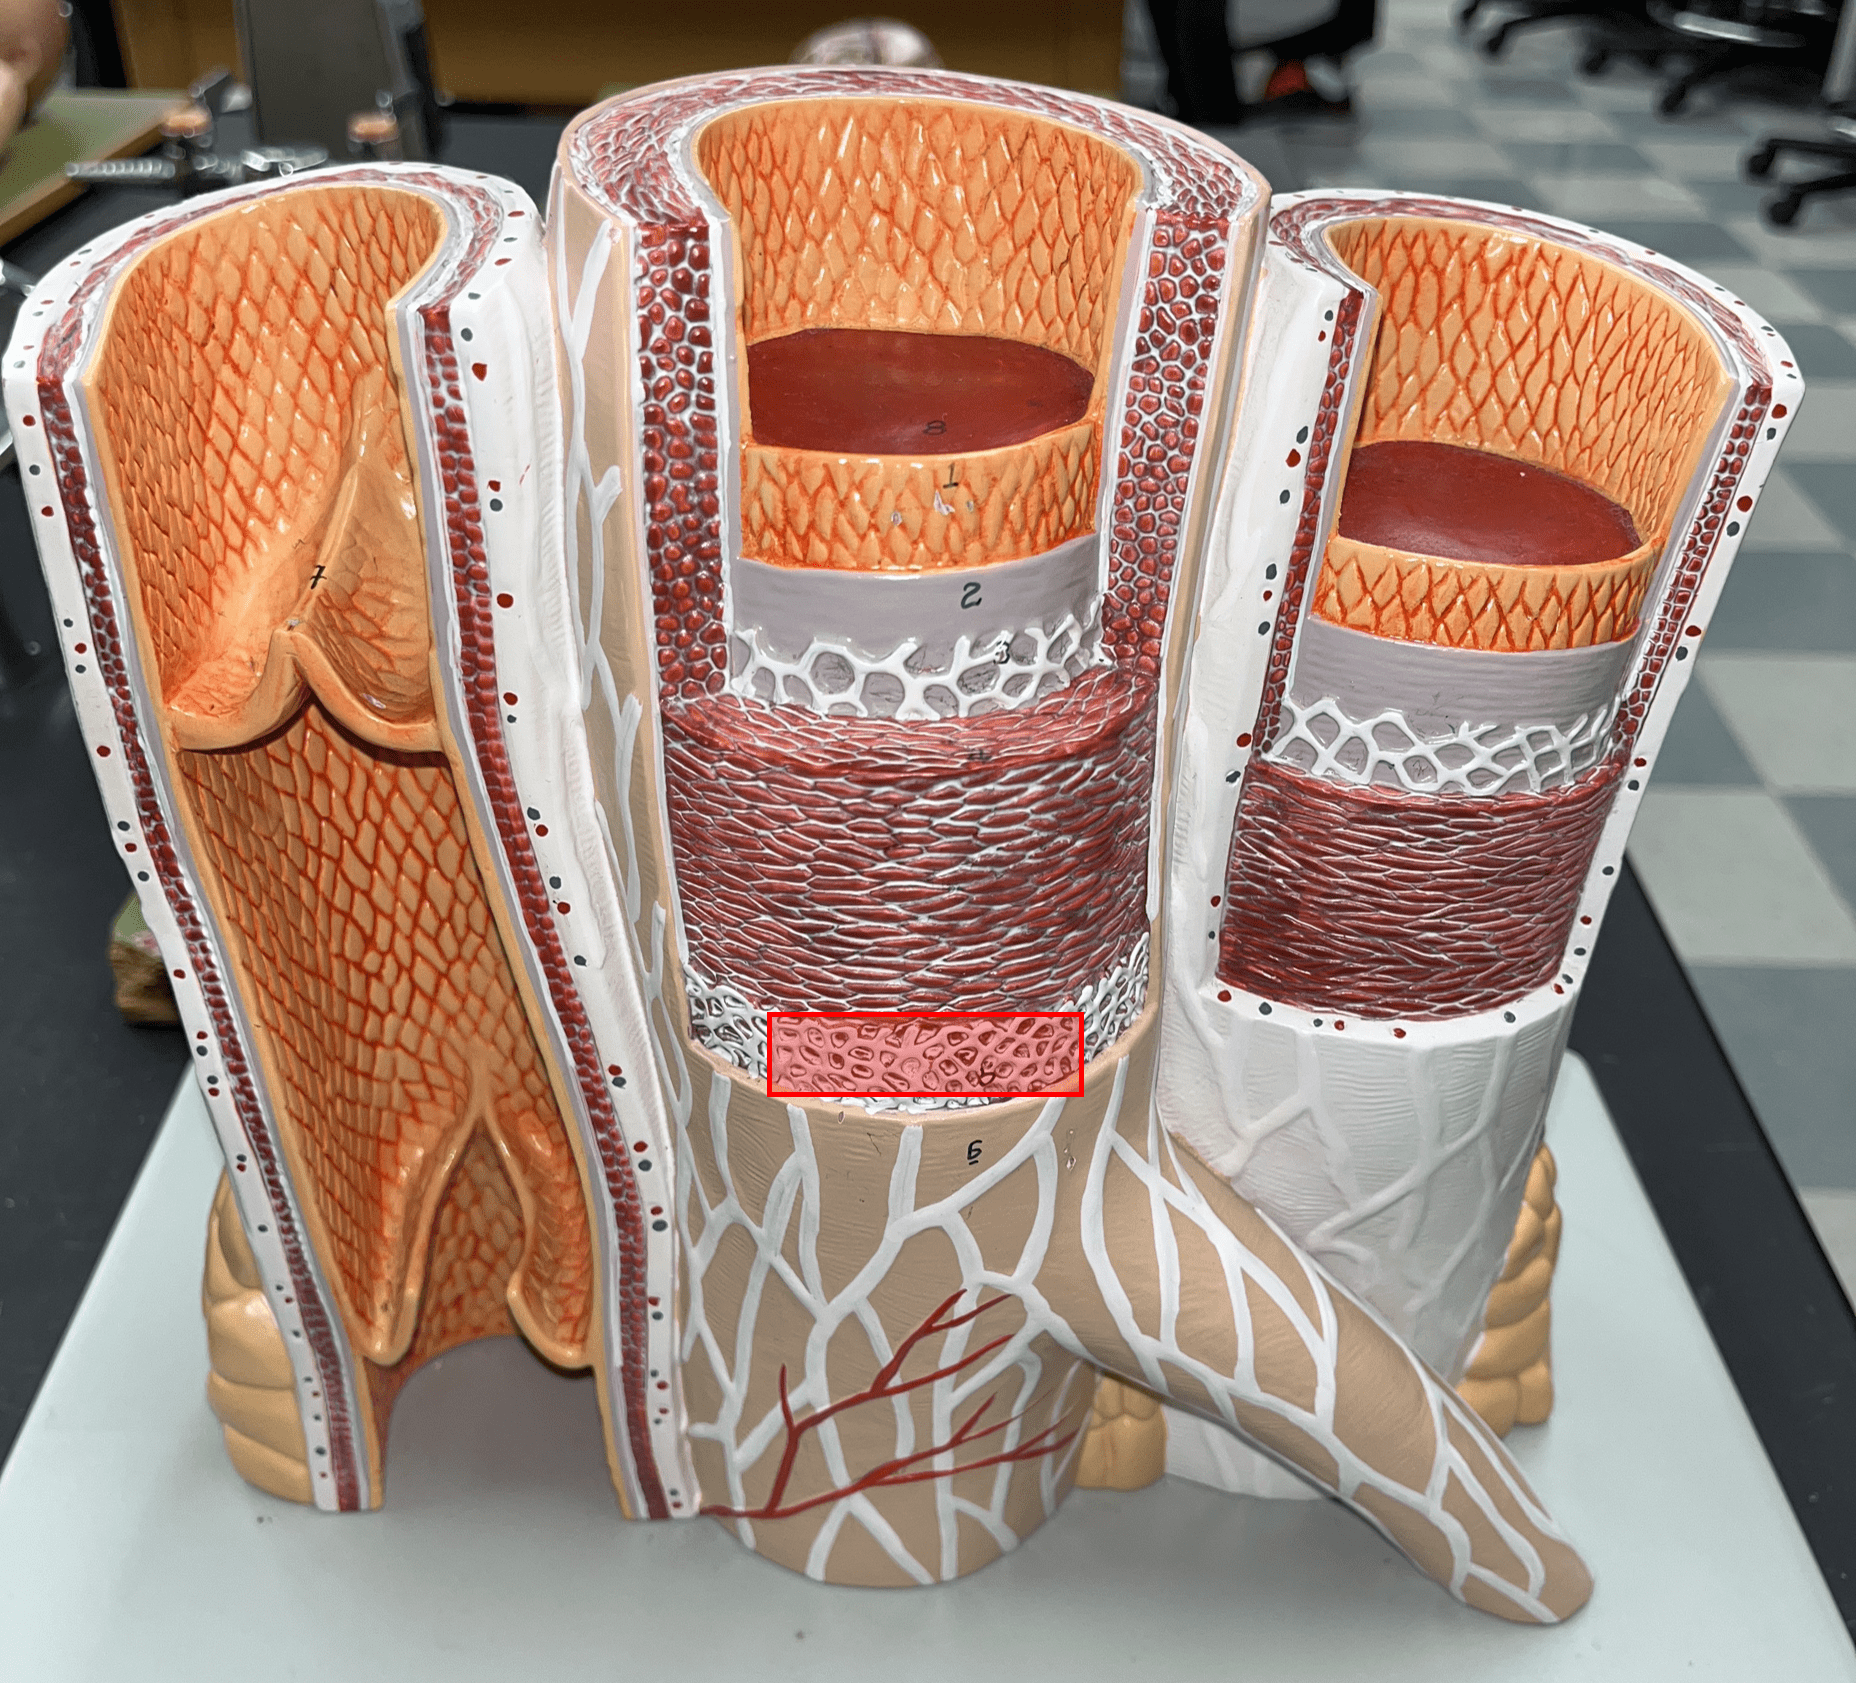

9

New cards

internal elastic membrane